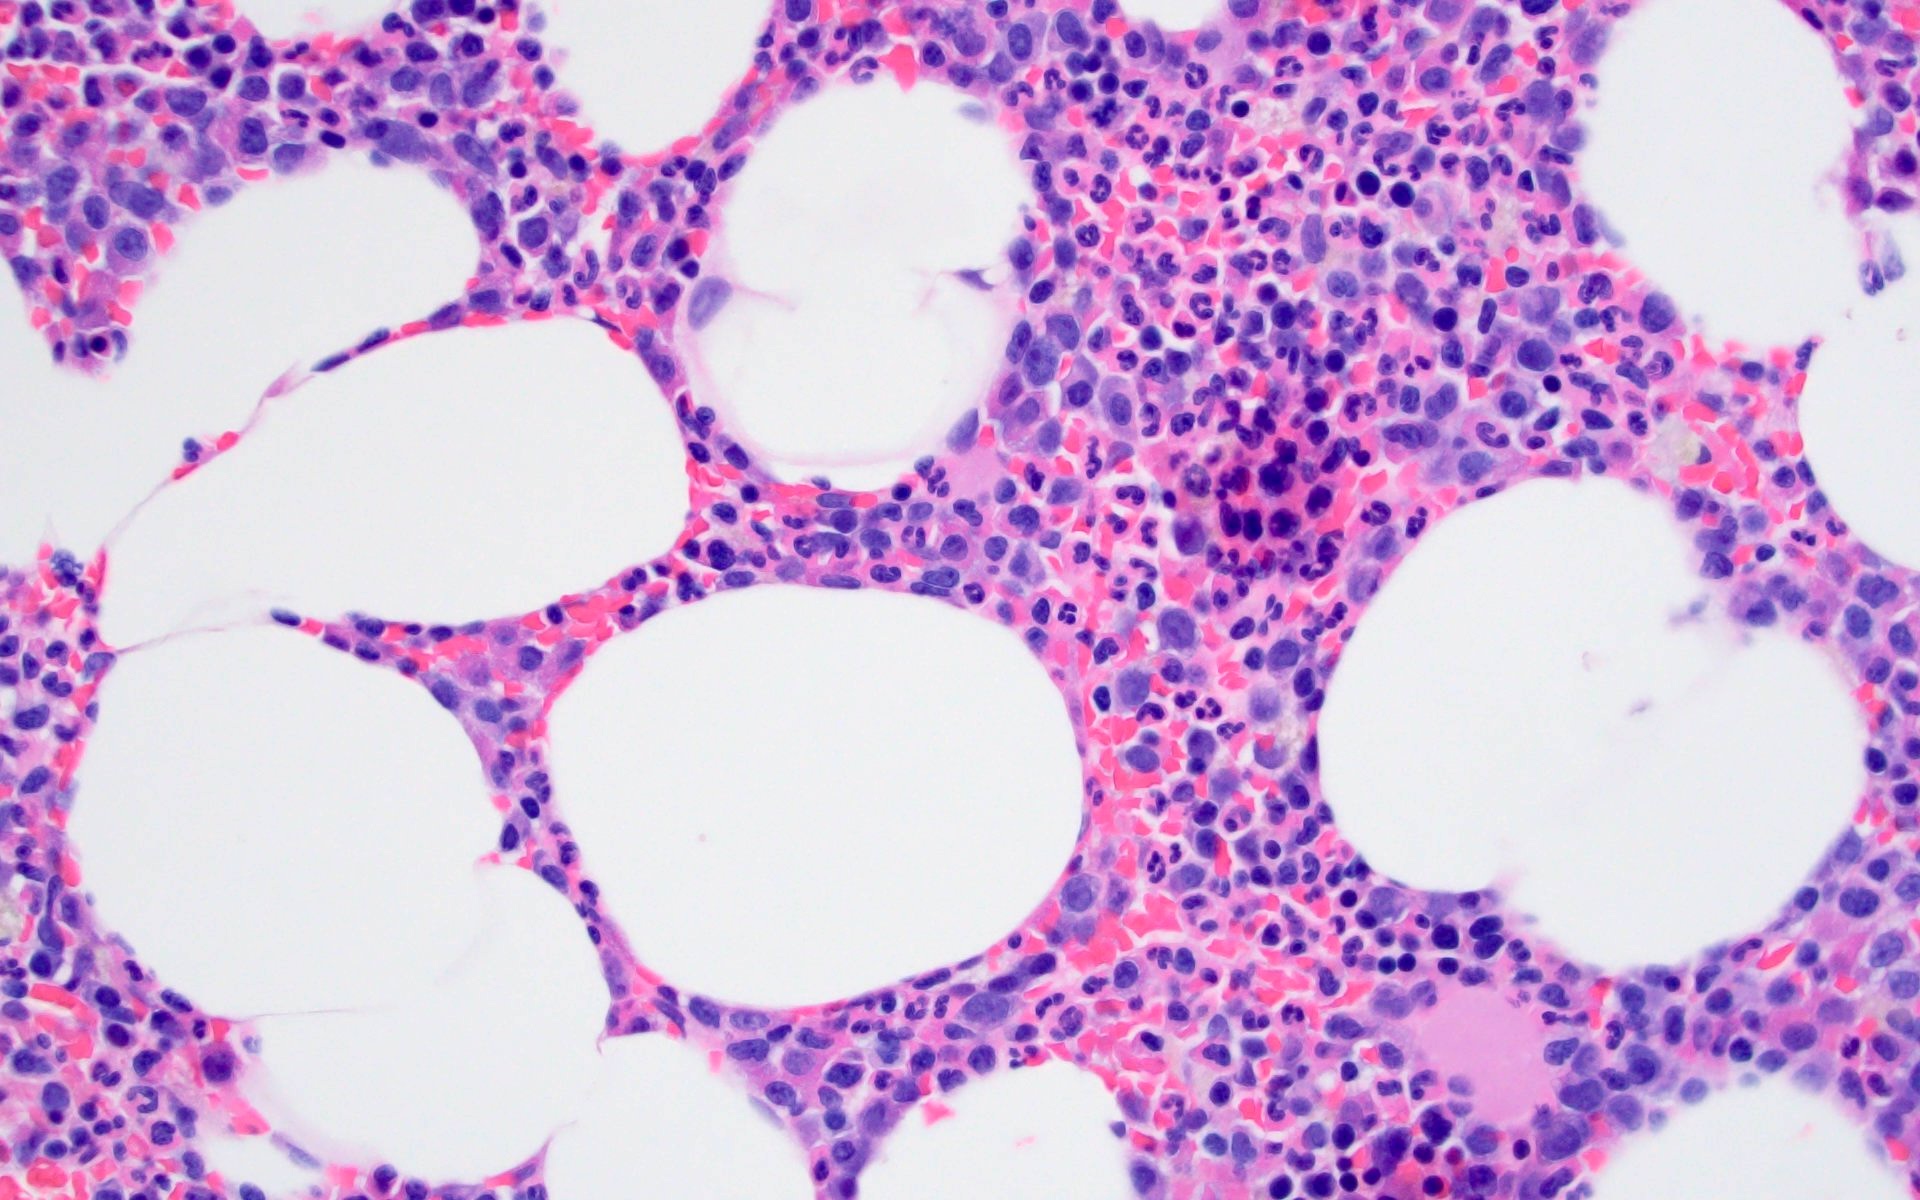

- Sheets of plasma cells with varying morphology ranging from normal appearing to large atypical plasma cells with prominent nucleoli to plasmablastic or anaplastic morphology (Am J Clin Pathol 2001;115:119, J Clin Oncol 2012;30:e91, Skeletal Radiol 2018;47:995)

- Russell or Dutcher bodies may be seen

- Associated amyloid deposition (Ann Diagn Pathol 2015;19:117)

Microscopic (histologic) images

A 43 year old man presents with nasal obstruction and epistaxis. Imaging showed a 2.2 cm nasopharyngeal mass. Nasopharyngeal and bone marrow biopsies were performed (see images above). Which of the following risk factors in this patient increases the chances of progression to multiple myeloma?

B. Bone marrow involvement is present in this case, which increases the risk of progression to multiple myeloma. Answers A, C and D are incorrect because the patient is young and the tumor size is < 5 cm with bland morphology (not plasmablastic / anaplastic), so none of the factors accounted for by these options increase risk of progression to multiple myeloma.